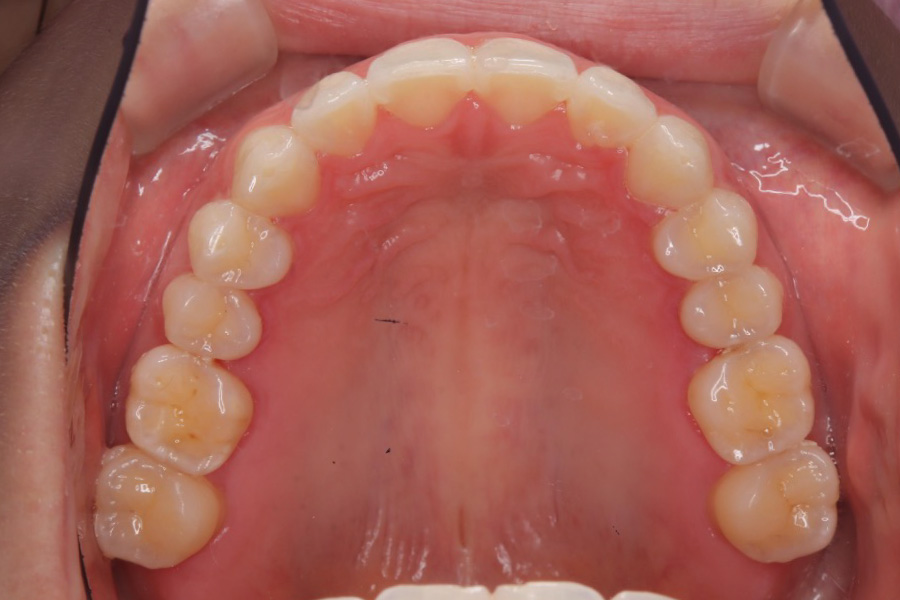

【20代女性】

歯のガタつきを

インビザライン矯正で治療したケース

治療後

主訴 ガタつき

期間 2年

費用 220,000円〜660,000円

治療内容 インビザライン矯正

非抜歯